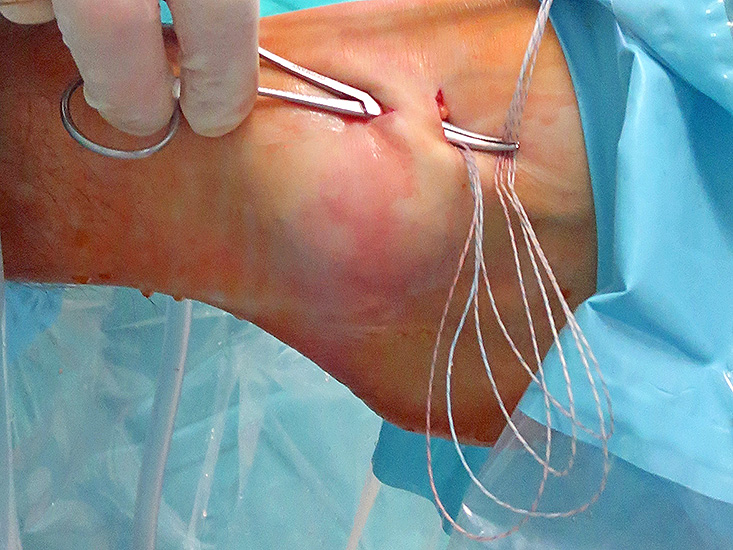

Operationstechnik

Nachfolgend wird die OP-Technik an einem rechten Sprunggelenk unter Verwendung von PEEK-Ankern veranschaulicht.

- Läsion der N. Äste des N. peroneus superficialis (N. cutaneus dorsalis medialis et intermedius): siehe oben. Der N. cutaneus dorsalis medialis ist bei schlanken Patienten bei forcierter Plantarflexions- und Inversionsstellung des Fußes oftmals gut unter Haut zu palpieren. Befindet sich das Arthroskop bereits über das anteromediale Portal im Gelenk, kann durch die Ausrichtung der Lichtquelle nach ventral der Verlauf der Nerven mittels Diaphanoskopie dargestellt werden. Der N. cutaneus dorsalis intermedius verläuft oftmals auf Höhe des distalen akzessorischen Zugangs und sollte daher sorgfältig dargestellt werden. Durch Einsetzen kleiner Langenbeck- oder Venenhaken während des gesamten Fadenmanagements bis einschließlich zur Fixation des Retinaculums kann eine Verletzung dieses Nervs vermieden werden.